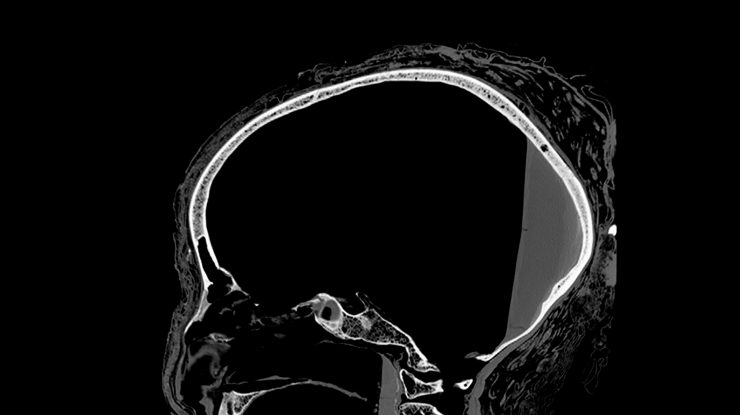

Oamenii de știință chinezi și americani au conceput un instrument de administrare a medicamentelor pentru cancerul cerebral

Specialiștii chinezi și americani au propus un nou sistem de administrare a medicamentelor care poate îmbunătăți tratamentul imunoterapeutic pentru cancerul cerebral, scrie agenţia de presă Xinhua.

Cercetătorii de la Universitatea Shandong și de la Universitatea din Wisconsin-Madison au conceput un hidrogel injectabil care conține nanoparticule care vizează celulele stem ale gliomului.

Acestea sunt considerate principalul vinovat pentru recidiva glioblastomului, o tumoare extrem de invazivă din creier, ce apare după îndepărtarea pe cale chirurgicală a tumorii iniţiale.